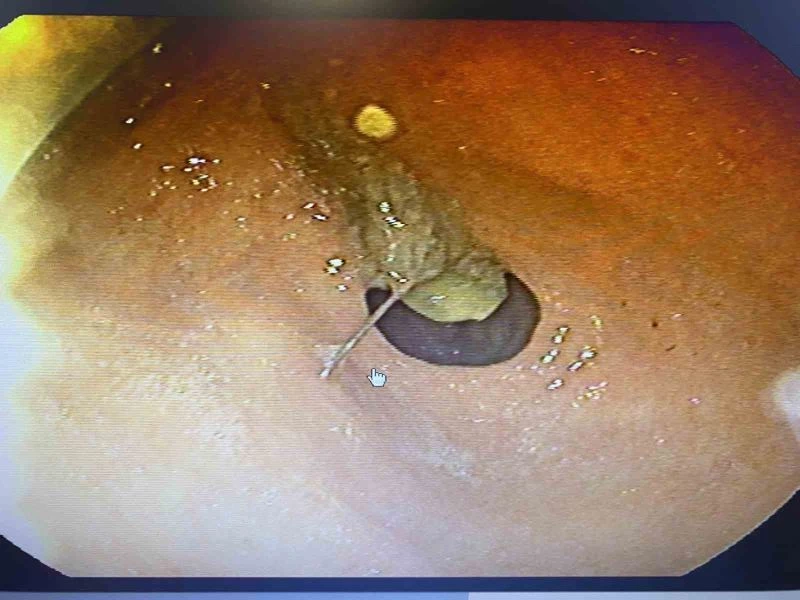

Gaziosmanpaşa’da yaşayan 2 çocuk annesi 45 yaşındaki Semiha Keçeci, iddiaya göre 23 Ocak’ta acelesi olduğu için başörtüsünü düzeltirken ağzına aldığı iğneyi hapşırınca yuttu. Yaklaşık 3,5 santimlik iğneyi yuttuğunu anlayan kadın şok olurken bir anda acı içinde kaldı. Başakşehir Çam ve Sakura Şehir Hastanesi acil servisinde tedavi altına alınan kadına hemen film çekildi. Toplu iğnenin mideye ulaştığı belirlenirken gerçekleştirilen endoskopik işlemle hastanın midesindeki iğne olduğu noktadan alındı. Keçeci, rahat bir nefes alırken, Başakşehir Çam ve Sakura Şehir Hastanesi Genel Cerrahi Bölümü’nden Op. Dr. İsmail Çalıkoğlu, gerçekleştirilen tedaviye ilişkin bilgi verdi. Mideye ulaşan iğne filmdeki görüntüsüyle gözler önüne serilirken, Op. Dr. Çalıkoğlu, özellikle çocuklarda yabancı cisim yutmalarına karşı uyardı.

İğne tutan hastasının durumuna ilişkin bilgi veren Başakşehir Çam ve Sakura Şehir Hastanesi Genel Cerrahi Bölümü’nden Op. Dr. İsmail Çalıkoğlu, “Burası Prof. Dr. Hasan Bektaş Hocamızın sorumluluğunda, 24 saat prensibiyle çalışan bir ünite. Bizlerin karşısına yabancı cisim yutmaları, soluk borusuna kaçmalar şeklinde gelebilmekte. Balık, tavuk kemiği ve ya diş protezleri en sık bizim gördüğümüz yutulan cisimler arasında. Ülkemizde de sıklıkla iğne yutulması, çivi, vida yutulması gibi şeylerle de sıklıkla karşılaşıyoruz. Hastamız bize geldiğinde başörtüsünü bağlamak için kullandığı iğnesini bir süre ağzına almak istediğini belirtti. Daha sonra bir hapşırma gelişmiş, aniden nefes çekme olayı olduğu için yemek borusuna bu iğne kaçmış. Bir ihtimal bu soluk borusuna da gidebilirdi böyle ani nefes almalarda o zaman soluk borusunun incelenmesi gerekirdi, akciğere kaçardı. Bu şartlarda yemek borusundan midesine doğru ilerleme olmuş. Bize başvurduğunda bu işin üzerinden 2-3 saat geçmişti, iğne yavaş yavaş ilerlemişti. Biz acil servilerde yaptığımız görüntülemelerde iğnenin henüz daha midede olduğunu, daha fazla ileriyle gitmediğini gördük. Akabinde hastamızı endoskopi ünitemize aldık, burada yaptığımız endoskopide de tam mide çıkışında mide mukozası dediğimiz en iç tabasına saplanmış şekilde gıda artıklarının arasında durduğunun gördük. Zor da olsa özel aletlerimizi kullanarak iğnemizi tuttuk, daha sonra endoskopi kanalının içinden hastamıza herhangi bir zarar vermeden dışarıya çıkarttık. Bu iğnenin hastamıza bu aşamaya kadar herhangi bir zarar vermediğini yemek borusunda, midesinde yırtılma yapmadığını gördük" diye konuştu.

İğnenin daha ileri bir noktaya gitmesi durumunda ameliyat gerekliliği oluşabileceğini söyleyen Op. Dr. Çalıkoğlu, “İğne saplandığı yerden daha da ilerlese midede, ince bağırsakta küçük de olsa delinmelere, bir ihtimal ameliyatla çıkarılması gerekliliği durumlarına ulaşabilirdi. Çok şükür ki hastamız şanslıydı, bize doğru zamanda gelmişti. Oyuncaklardaki küçük boncuklar, nazar boncukları, tespih tanesi, nohut, küçük parçalı oyuncaklar olabilir. Bunlar hep çocuklarımızın özellikle yemek borusuna gitse bile soluk borusuna giderek çok ciddi nefes durmaları ve sağlığı tehdit edici durumlar oluşabiliyor. Piyasada açıkta olan bazı deterjan ürünleri olabiliyor, bunları su şişelerine biriktirenler ve ya evde ne kadar deterjan kullanacaksa onları bardağa koyup bekletenler olabiliyor bunları da çocuklarımız, büyüklerimiz yanlışlıkla içebiliyor. Bunlara azami dikkat etmemiz lazım. İğne tutacaksa ağzında, vidalama yapacaksa tamir yaparken ağzına çivi almalar olabiliyor. Ağzımızı bunlarda kullanmamamız lazım çünkü aniden hapşırma, öksürmeyle ve ya kayma şekliden biz bunları tutamıyoruz. Yemek borumuza doğru inmeye başlıyor. İğnemiz 3-4 cm boyutunda toplu bir iğneydi. Ağırlığı toplu tarafında olduğu için ters doğru inmiş, hastamızda boğazında ve göğsünde acıtmalar yapmış" ifadelerini kullandı.